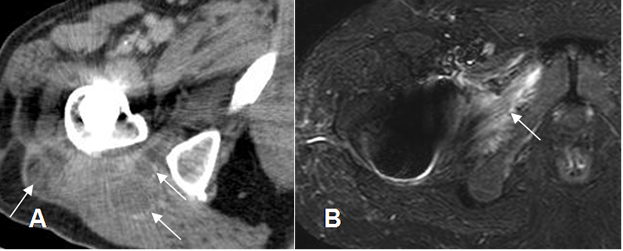

Fig 66. Artritis séptica.

A: TAC axial con contraste. Artritis como complicación de prótesis en la cabeza femoral. Inflamación de tejidos blandos, con incipiente formación de abscesos, cuyos bordes captan el contraste. (Flechas).

B: RM axial en STIR. Extensión de los cambios inflamatorios, hacia el músculo obturador externo.